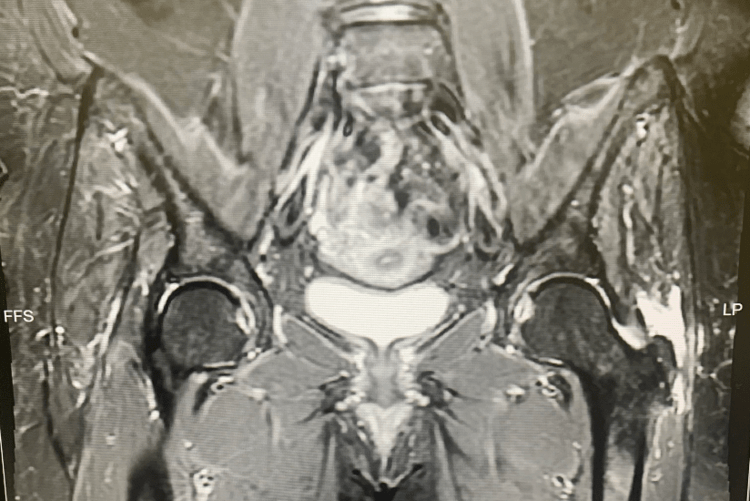

ac Fullthickness tear of gluteus medius in a 71yearold woman. a... Download Scientific Diagram